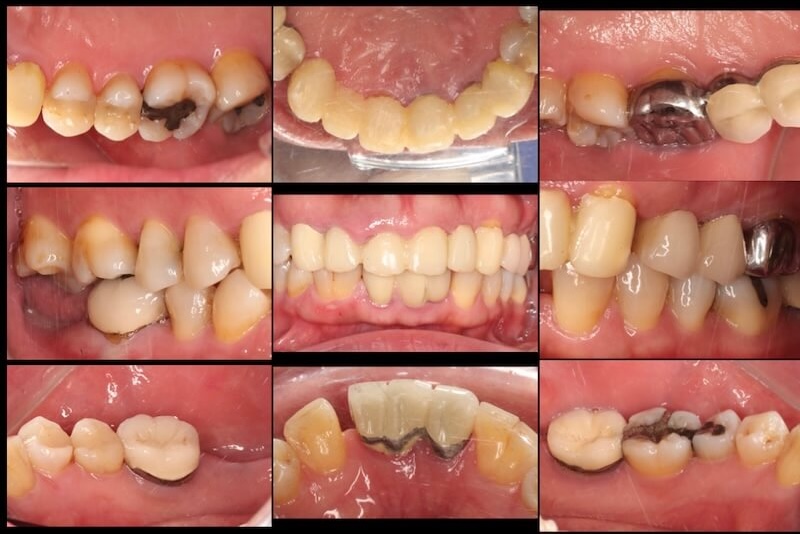

口內的檢查可以看到,在上顎前面六顆假牙,牙齦明顯腫起來。這可能來自兩個原因:

第一個就是 Ms.H 長期服用高血壓藥物控制血壓,最常見的就是『鈣離子通道阻斷劑』(Calcium Channel Blocker, CCB),例如脈優(Norvasc)。牙齦腫大就是此類藥物的副作用之一。

另外一個原因就是假牙邊緣比較深入牙齦深處,侵犯到牙齒的生物寬度,也會產生類似這樣的表徵。

拆除舊假牙換上臨時假牙之後,開始進入牙周病的療程。我們會先將治療前口內狀況完整記錄,詳細分析每一顆牙齒的牙周狀況。